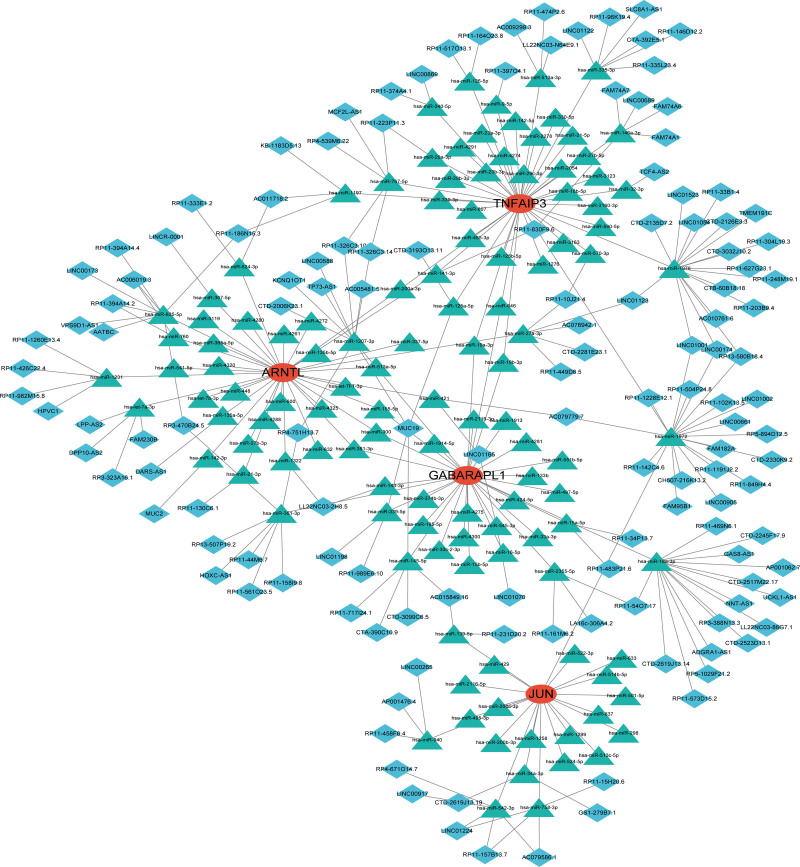

3.7. Construction of a ceRNA network based on feature genes

Based on the interaction of the 4 feature genes with relevant miRNAs, lncRNAs by using miRanda (http://mirtoolsgallery.tech/mirtoolsgallery/node/1055), miRDB (https://mirdb.org/), TargetScan (https://www.targetscan.org/vert_72/), and spongeScan (https://spongescan.rc.ufl.edu/) databases, we constructed a regulatory network integrating multifactor including miRNA and lncRNA to explore the underlying regulatory mechanism of the expression of these feature genes at both transcriptional and post-transcriptional levels (Fig. 9).